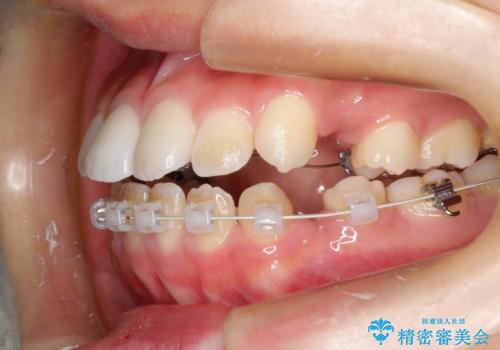

ハーフリンガル 半分裏側矯正による上下前突の抜歯矯正治療

- 20代女性

- 矯正装置

- ハーフリンガル

- 上下左右4本の第1小臼歯を抜歯する、抜歯矯正を計画した。

抜歯矯正により前歯の位置が後ろに下がり、わずかではありますが、口元に改善がみられ、歯並びもきれいに整いました。